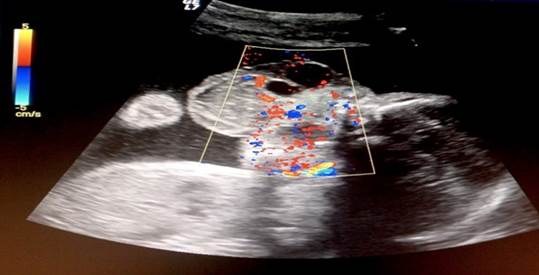

Se le realizó ecografía tridimensional (Figura 3 y 4) y se indicó realizar resonancia magnética nuclear prenatal que respaldara el diagnóstico inicial y para evaluar la extensión; se planteó el caso a cirugía pediátrica para planificación de la resolución posnatal. Se realizó un procedimiento diagnóstico prenatal invasivo, obteniendo como resultado cariotipo normal (46, XX). A las 26 semanas y 4 días se le realizó ecocardiografía fetal encontrándose corazón anatómico y funcional normal y perfil hemodinámico materno fetal adecuado a edad gestacional; además, se evidenció polihidramnios. En el siguiente control ecográfico se evidenció un crecimiento progresivo del tumor hasta 82 x 61 mm, con un polihidramnios estable, y sin evidenciar otro signo de compromiso fetal. Se planificó conducta expectante hasta el término y el manejo periparto pertinente.

La paciente ingresó a urgencias a las 28 semanas y 4 días por presentar rotura prematura de membranas y se evidenció en la ecografía el feto sin actividad cardíaca. Se atendió parto vaginal en el que se obtuvo recién nacido sin signos vitales con peso de 950 gramos y talla de 45 cm; se corroboró desde el punto de vista macroscópico los hallazgos descritos en la evaluación ecográfica prenatal (Figura 5, 6, 7, 8). Cabe señalar, que por limitaciones técnicas no fue posible realizar el estudio de anatomía patológica correspondiente.

Figuras 5 y 6 Aspecto externo de recién nacido muerto, con lesión exofítica muy vascularizada, que ocupa el macizo facial medio y piso de la boca.